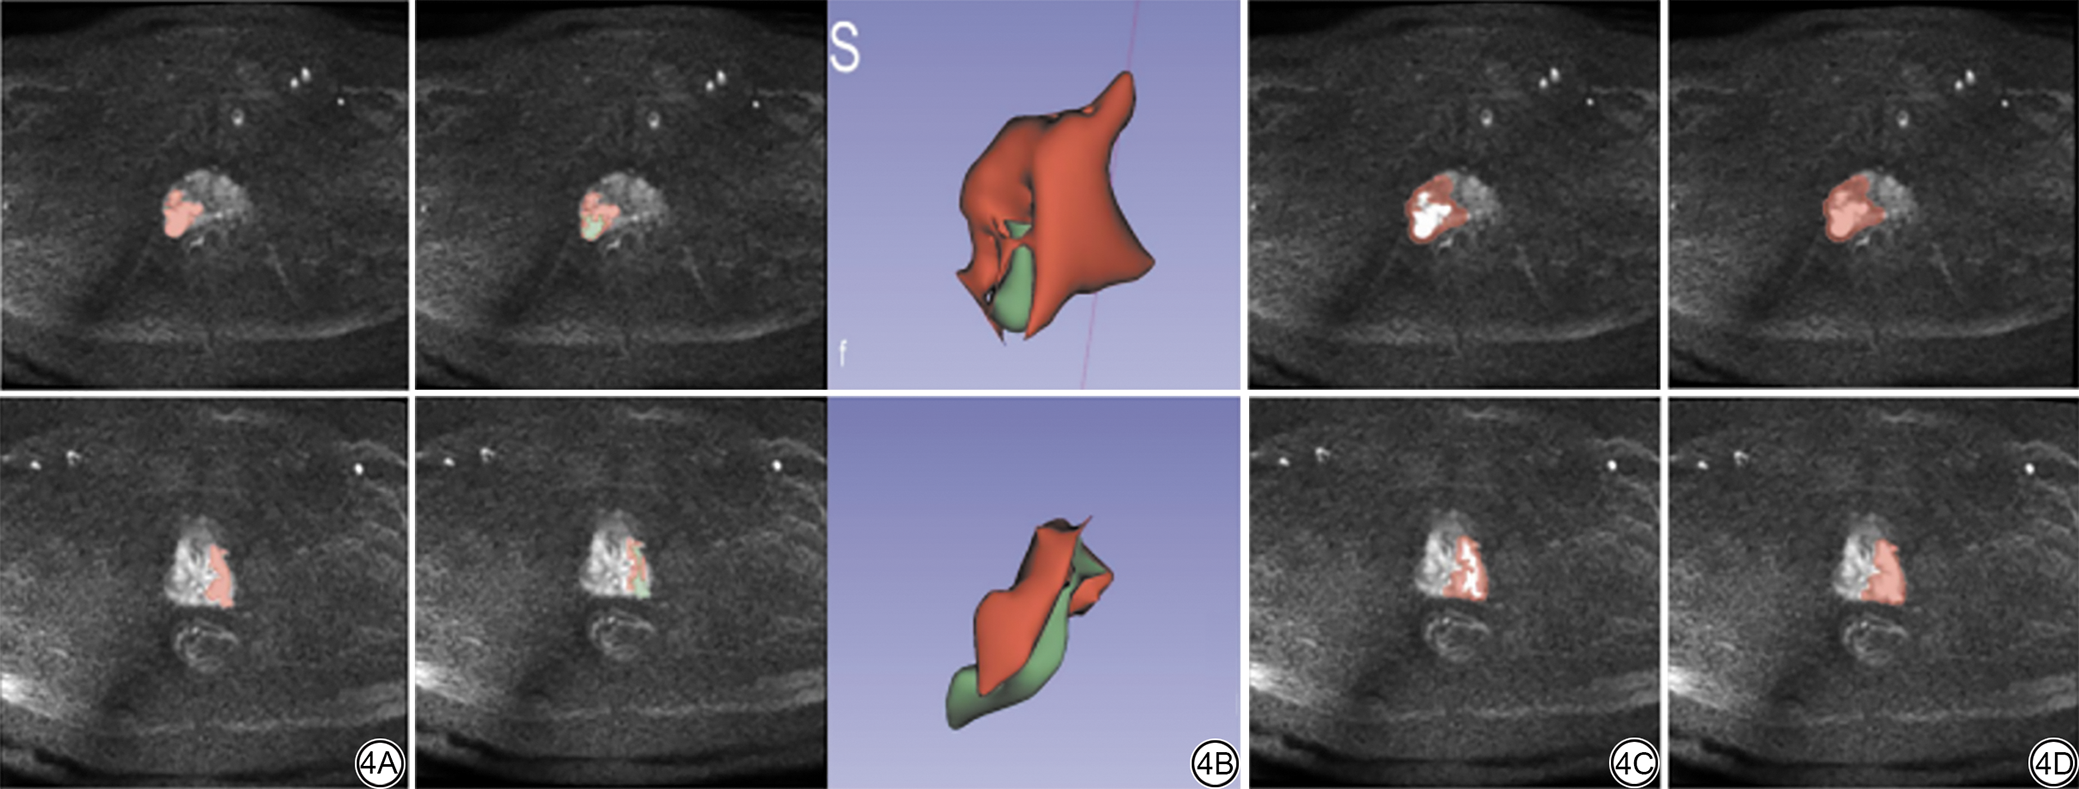

本研究采用轮廓系数(silhouette coefficient)进行最佳聚类评估。我们选择k=2作为最佳聚类数。采用Scikit-Learn中的K均值聚类算法(K-means clustering algorithm),对每个样本的MRI序列T2-DWI-增强三个模态中VOI的体素值进行聚类。轮廓系数与聚类散点图如图2图3所示,PCa病灶勾画示意图如图4所示。采用Python 3.7平台的PyRadiomics工具包(版本3.0.1)[24],分别从两个影像亚区(habitat1、habitat2)中独立提取影像组学特征。在队列层面,通过将ROI细分为亚区进行聚类分析,由于生物学异质性,部分病例未形成全部两个亚区聚类。针对此问题,采用跨患者特征均值计算法对两组影像亚区特征进行融合。基于筛选后的亚区特征,在训练组中构建分类模型,并在验证组中进行效能验证。

图4  病灶勾画示意图。4A:瘤内区域勾画ROI;4B:瘤内区域生境分割ROI与VOI;4C:瘤周区域ROI;4D:瘤内加3 mm瘤周ROI。ROI:感兴趣区;VOI:感兴趣体积。

Fig. 4  Schematic representation of lesion delineation. 4A: Intratumoral ROI delineation; 4B: Habitat segmentation of intratumoral ROI and VOI; 4C: Peritumoral ROI; 4D: Intratumoral ROI with 3 mm peritumoral expansion. ROI: region of interest; VOI: volume of interest.